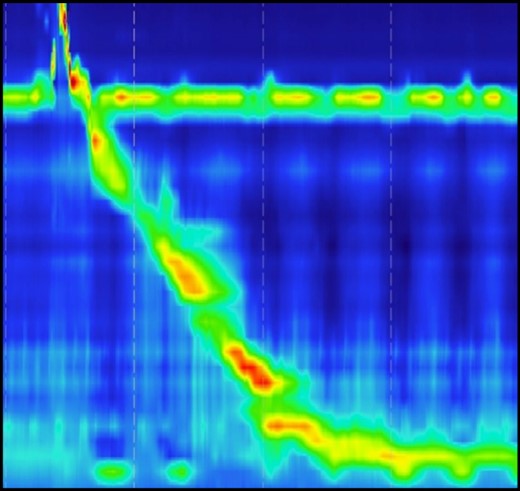

A 72-year-old woman with a past medical history of coronary artery disease and chronic gastroesophageal reflux disease (GERD) with hiatal hernia status postsurgical correction by Nissen’s fundoplication 20 years ago, presented with worsening episodes of intermittent dysphagia, heartburn, and postprandial cough of ~2 years duration but worsening symptoms over the past 2 months. She denies any symptoms of food regurgitation, nausea, vomiting, appetite, or weight changes. Upon her initial clinic evaluation, she had normal vital signs and unremarkable findings on the physical exam. The decision was made to start her empirically on a proton pump inhibitor, assuming her symptoms are related to GERD, to which she did not respond appropriately. A subsequent upper endoscopy revealed a large epiphrenic wide-mouthed ED (Fig. 1). Additionally, an esophagram showed a 6.0 × 5.0 cm epiphrenic ED with a 3.3 cm neck (Fig. 2). High-resolution esophageal manometry (HREM) was performed; thereafter, revealing a normal motility pattern (Fig. 3). She was then referred to cardiothoracic surgery for consideration of surgical repair. She was initially advised to follow a dysphagia-specific diet and wait conservatively on her symptoms, but no changes were observed in her clinical course over 6 months. The patient subsequently underwent a successful uncomplicated esophageal diverticulectomy with myotomy, conducted through a lateral thoracotomy. During surgery, an esophagogastroduodenoscopy (EGD) revealed an ED at 35 cm in the gastroesophageal (GE) junction at 40 cm in the epiphrenic region. A standard posterior lateral thoracotomy was performed in the serratus-sparing fashion, and the pleural space was entered at the seventh intercostal space. The esophagus was encircled with a Penrose drain lifting it up, and it was freed from the periaortic tissue, and the ED cleared off all muscle fibers. The diverticulum was excised from the esophagus using a purple load stapler with an EGD scope in place to prevent esophageal narrowing. A myotomy was performed from the GE junction proximally, with negative leak testing. The muscle layer was then imbricated over the area of diverticulectomy, and a chest tube was inserted for drainage. A postoperative esophagram confirmed no presence of an ED (Fig. 4). Immediately after the surgery, the patient had a complete resolution of her symptoms, and during her 1-year follow-up visit, she remained asymptomatic.

Normal motility pattern on high-resolution manometry test in a patient with epiphrenic ED.